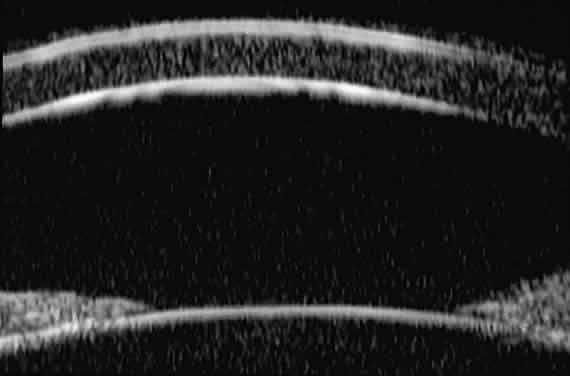

The role of UBM in the preoperative assessment of eyes with cataract is as yet unknown. In certain eyes, however, UBM may reveal features or abnormalities that could alter the ophthalmologist's surgical approach. Postoperatively, UBM can show the size and location of an intraocular lens (IOL) and the positioning of the haptics. A posterior chamber IOL appears on UBM as a highly reflective plate (corresponding to the lens optic) in the retropupillary plane with reverberation artifacts behind it (Fig. 17A). In contrast, an anterior chamber IOL appears on UBM as a sonoreflective plate located anterior to the pupillary plane (see Fig. 17B). In most eyes with a posterior chamber IOL, UBM can show whether the haptics are in the capsular bag (Fig. 18A), in the ciliary sulcus (see Fig. 18B), or in some other anatomic location12 (e.g., resting on the peripheral iris or secured with sutures to the sclera). The haptics are easier to locate if they are made of polymethyl-methacrylate than if they are made of proline because the former has a stronger reflectance.

Fig. 17. Composite UBM images of intraocular lenses. A. Posterior chamber IOL. B. Anterior chamber IOL.